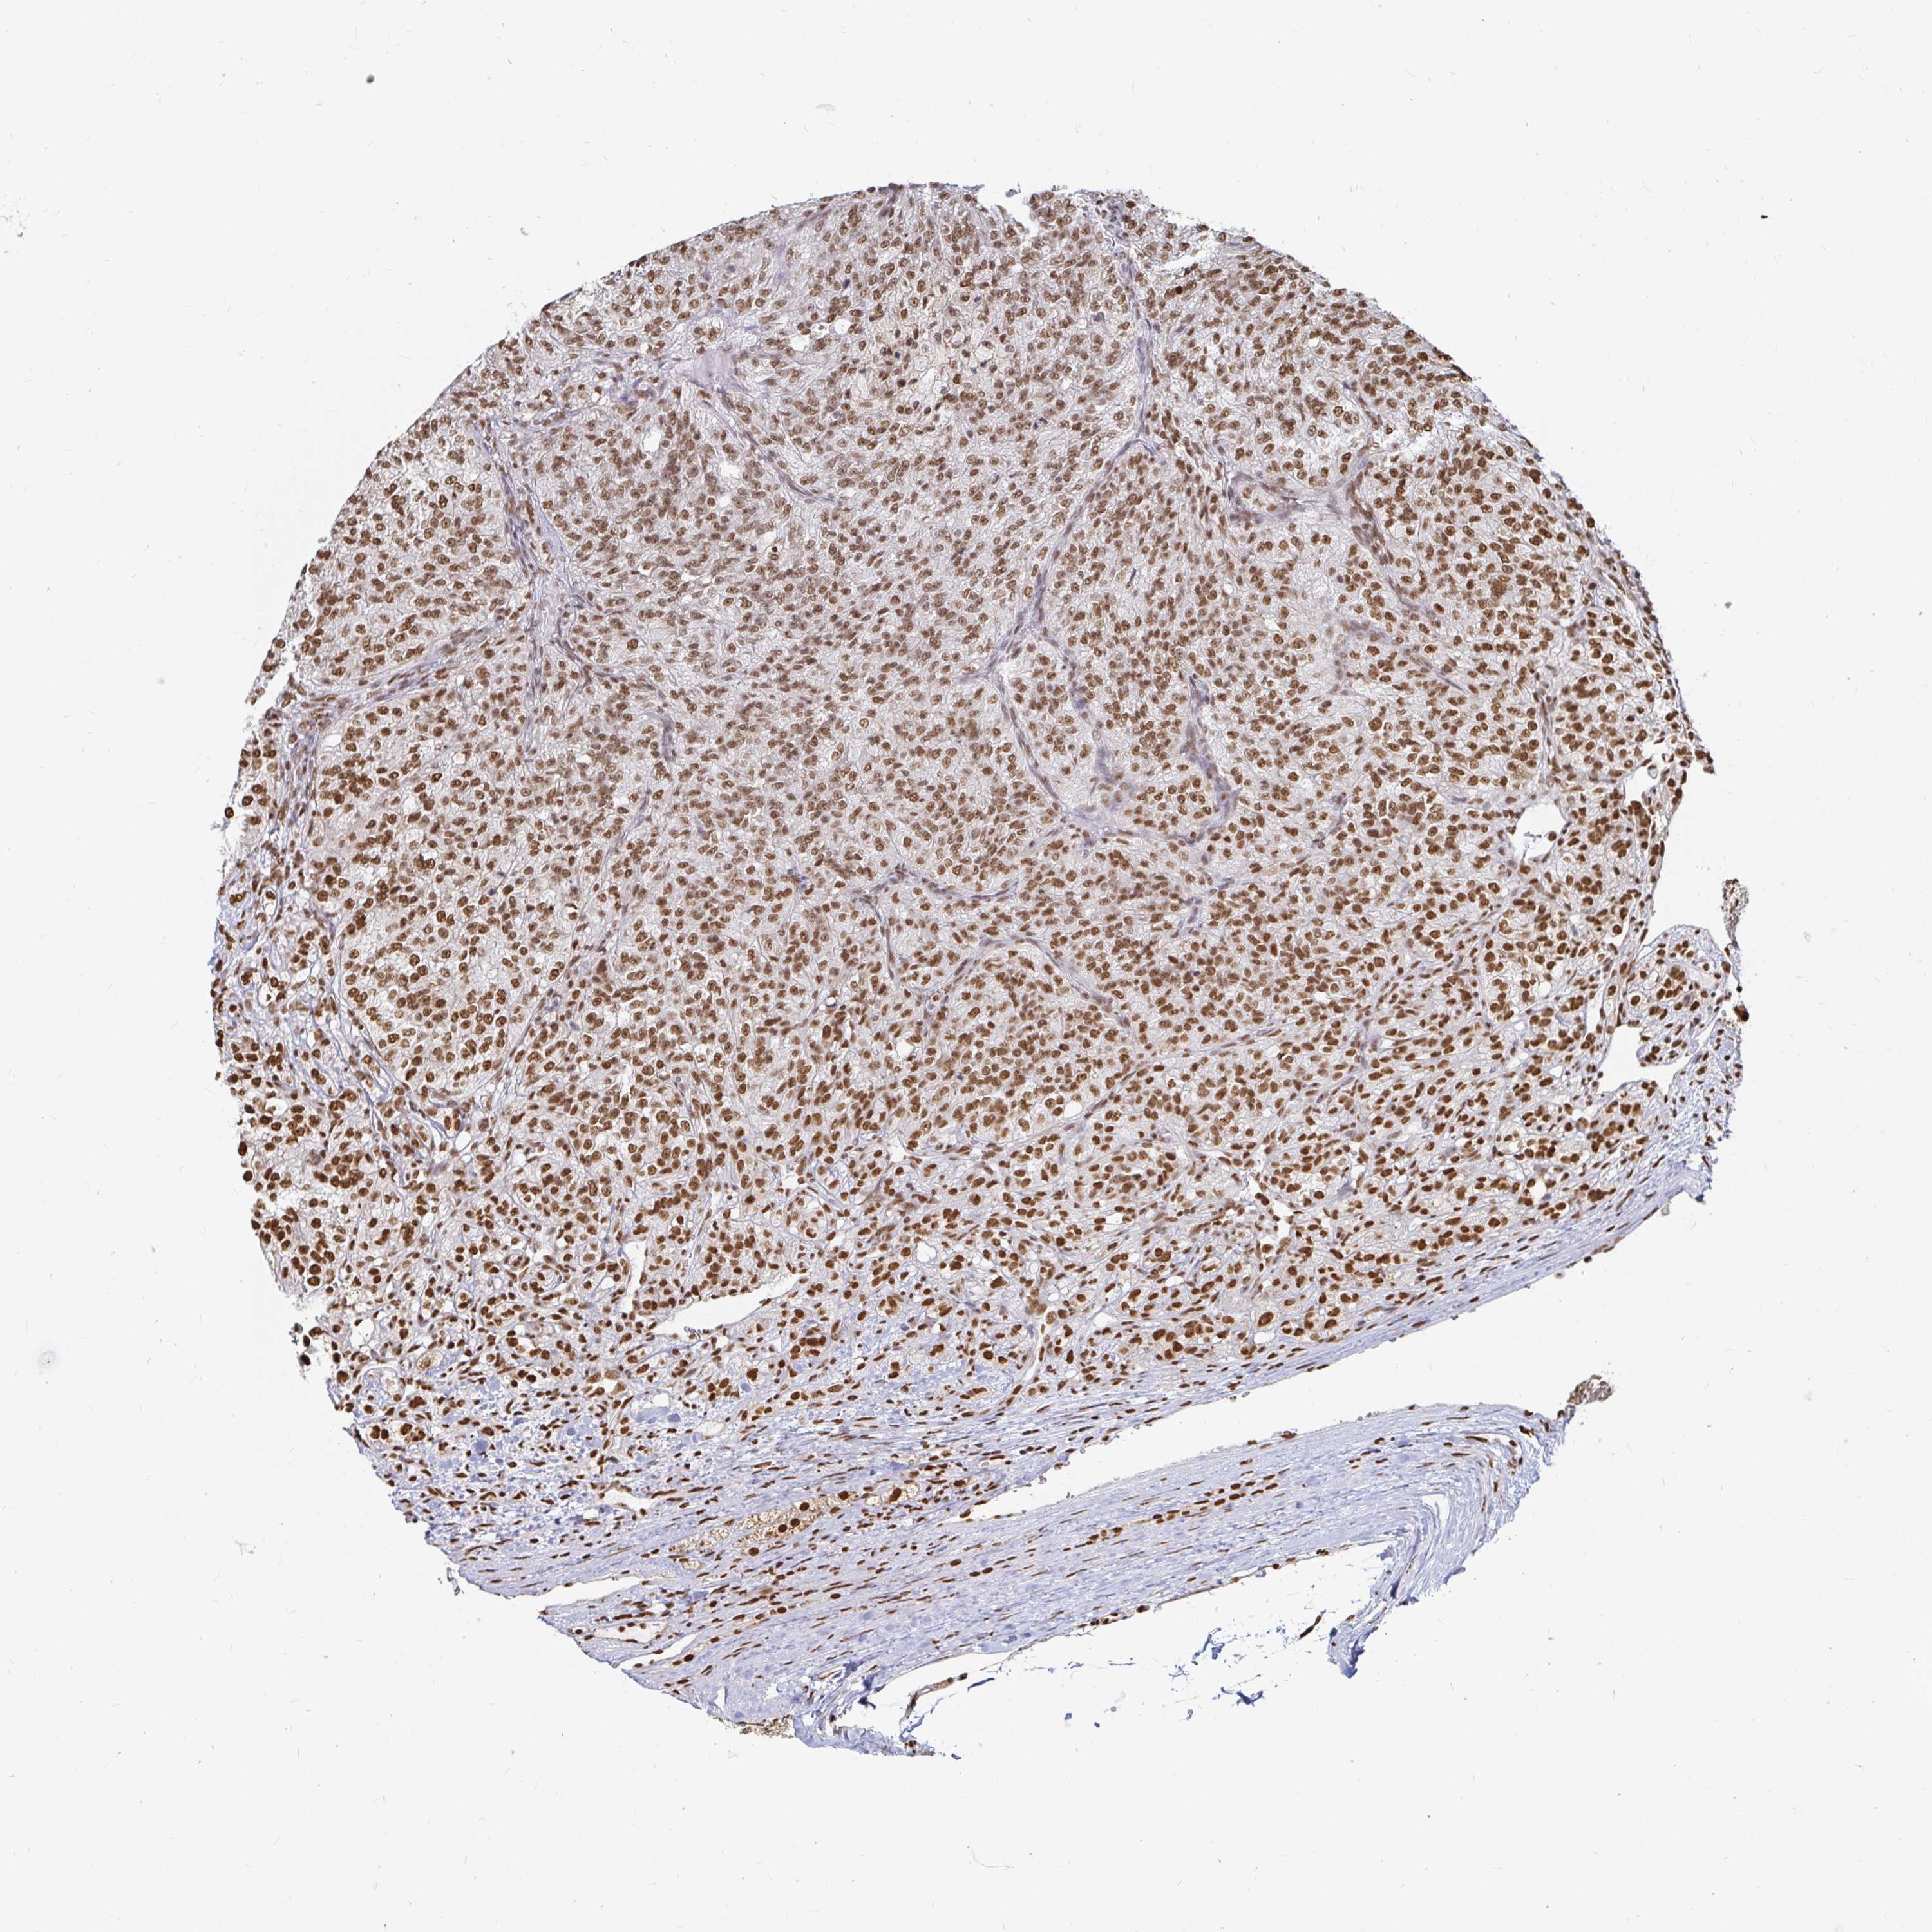

KIDNEY RENAL CLEAR CELL CARCINOMA (VALIDATION) - Interactive survival scatter ploti

The Survival Scatter plot shows the clinical status (i.e. dead or alive) for all individuals in the patient cohort, based on the same data that underlies the corresponding Kaplan-Meier plots. Patients that are alive at last time for follow-up are shown in blue and patients who have died during the study are shown in red.

The x-axis shows the expression levels (FPKM) of the investigated gene in the tumor tissue at the time of diagnosis. The y-axis shows the follow-up time after diagnosis (years). Both axes are complimented with kernel density curves demonstrating the data density over the axes. The top density plot shows the expression levels (FPKM) distribution among dead (red) and alive patients (blue). The right density plot shows the data density of the survived years of dead patients with high and low expression levels respectively, stratified using the cutoff indicated by the vertical dashed line through the Survival Scatter plot. This cutoff is automatically defined based on the FPKM cutoff that minimizes the p-score. The cutoff can be changed by dragging the vertical line or by entering a cutoff value in the square labeled "Current cut-off".

Under the Survival Scatter plot the p-score landscape (black curve; left axis) is shown together with dead median separation (red curve; right axis). Dead median separation is the difference in median mRNA expression between patients who have died with high and low expression, respectively. It is calculated as follows: median FPKM expression of dead patients with high expression - median FPKM expression of dead patients with low expression. This is intended to aid the user in visually exploring custom cutoffs and the associated p-scores and dead median separation.

Individual patient data is displayed and can be filtered by clicking on one or more of the category buttons on the top of the page. Categories describing expression level and patient information include: high, low, alive, dead, female, male and tumor stages. The scale of the x-axis can be toggled between linear and log-scale by clicking on the "x log" button. Mouse-over function shows TCGA ID, patient information and mRNA expression (FPKM) for each patient.

& Survival analysisi

Kaplan-Meier plots summarize results from analysis of correlation between mRNA expression level and patient survival. Patients were divided based on level of expression into one of the two groups "low" (under cut off) or "high" (over cut off). X-axis shows time for survival (years) and y-axis shows the probability of survival, where 1.0 corresponds to 100 percent.

HNRNPU is not prognostic in Kidney Renal Clear Cell Carcinoma (validation)

Best expression cut offi

Based on the FPKM value of each gene, patients were classified into two groups and association between prognosis (survival) and gene expression (FPKM) was examined. The best expression cut-off refers the FPKM value that yields maximal difference with regard to survival between the two groups at the lowest log-rank P-value. Best expression cut-off was selected based on survival analysis .

When clicking on this number, the vertical dashed line indicating cut-off, the interactive survival plot, and the Kaplan-Meier curve will be adjusted to show results based on the best expression cut-off.

: 133.42

TCGA RNA samplesi

RNA-seq data is reported as average FPKM (number Fragments Per Kilobase of exon per Million reads), generated by the The Cancer Genome Atlas (TCGA) .

Normal distribution across the dataset is visualized with box plots, shown as median and 25th and 75th percentiles. Points are displayed as outliers if they are above or below 1.5 times the interquartile range. FPKM values of the individual samples are presented next to the box plot.

Average pTPM 159.5

Number of samples 100